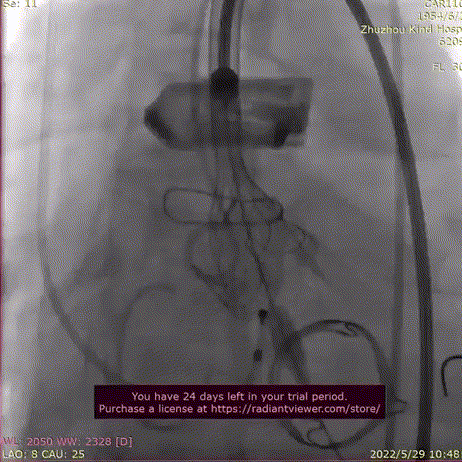

TaurusElite输送系统轻松过弓、跨瓣,AV23瓣膜瓣环平面定位释放,到工作位后造影显示瓣膜形态、位置良好。

输送系统过弓跨瓣

释放到工作位观察